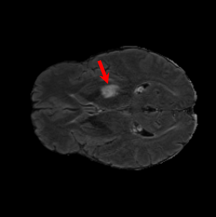

6.3 When does X-Diffusion Fail?

To see when and how X-Diffusion fails, we conducted an experiment on healthy brains (no tumour) using the IXI dataset, by running an X-diffusion trained on the BRATS brain tumor dataset. Our X-Diffusion achieved a PSNR of 35.86 dB on the IXI dataset despite being trained on the BRATS dataset. We then ran the tumour segmenter on the set of 582 healthy scans and corresponding generated MRIs. The segmenter predicted tumours in 9.9% of the real healthy brains and in 11.3% of the generated brain MRIs. Some of these tumor hallucination examples from X-Diffusion generation are shown in Figure 9.